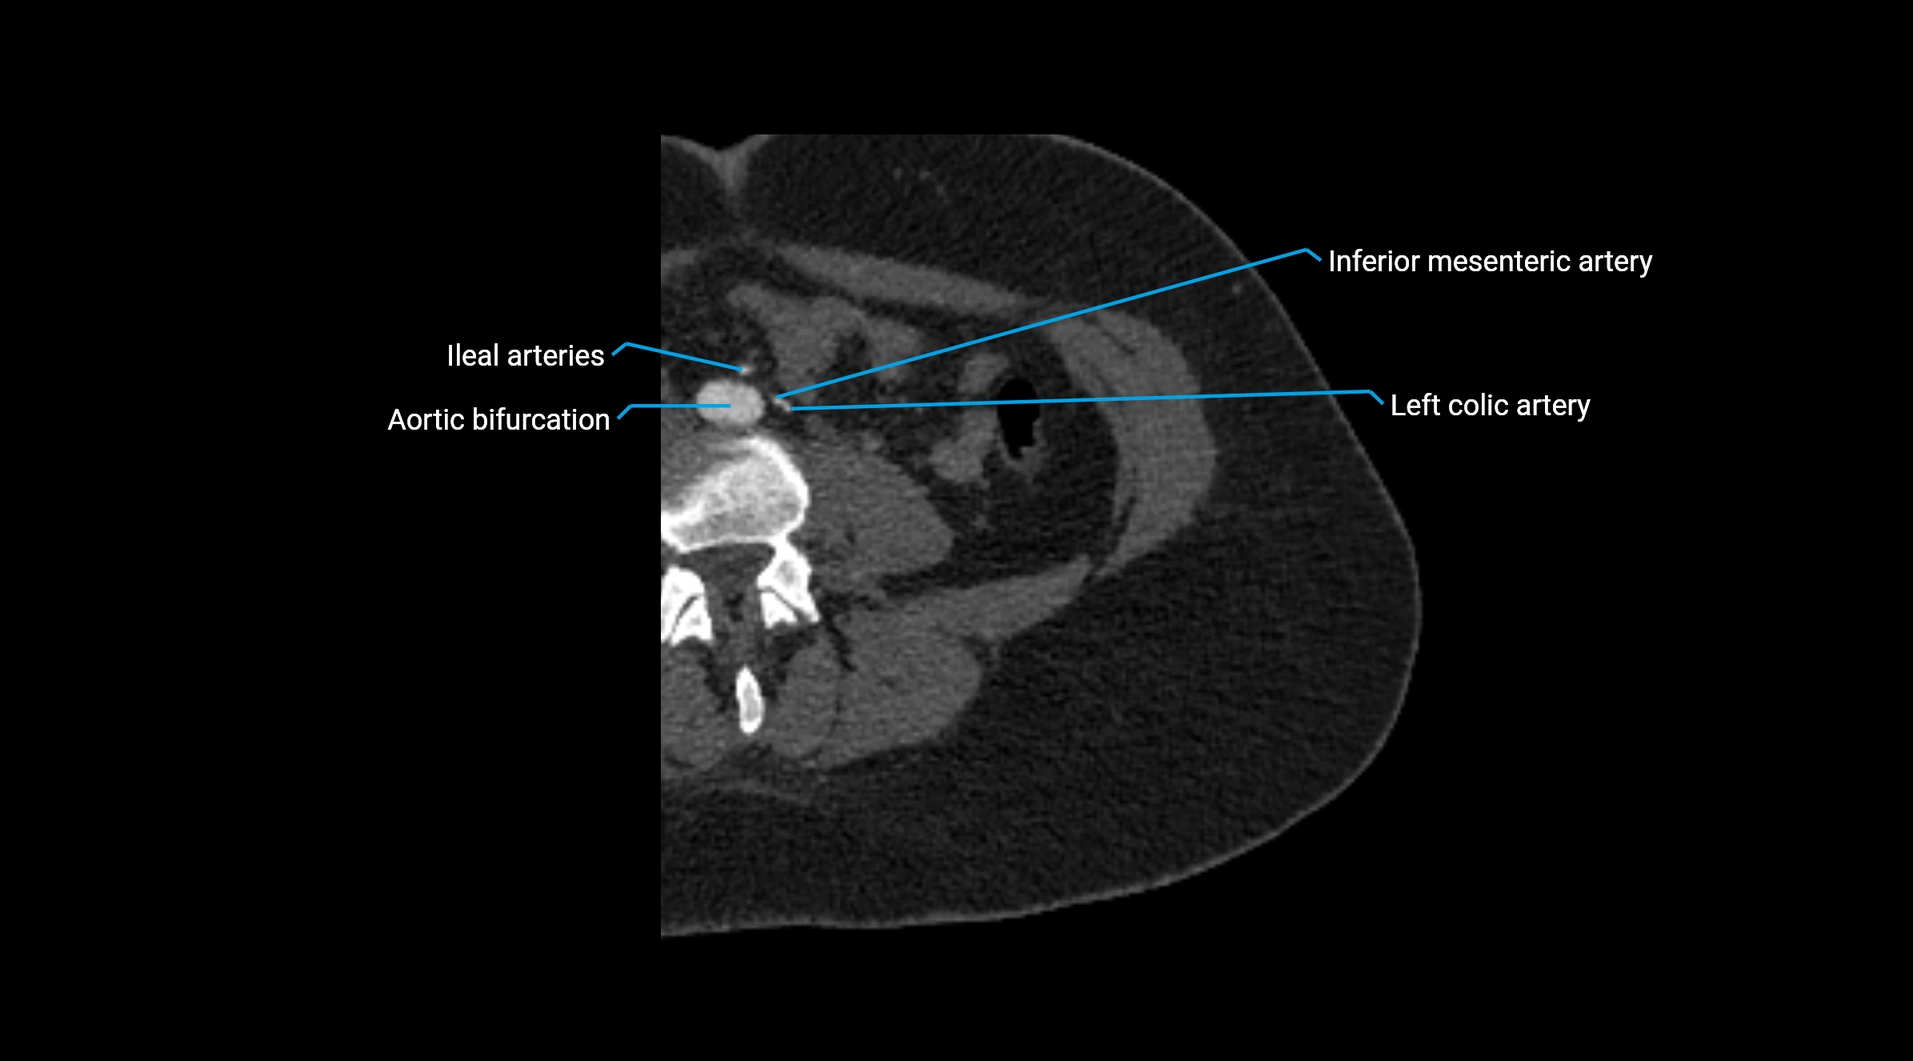

CT images

image

Contrast-enhanced CT (CTA):

• Gold standard for abdominal aortic imaging

• Provides excellent detail of lumen, wall, aneurysm, thrombus, and branch vessels

• Multiplanar and 3D reconstructions help in aneurysm measurement, stent graft planning, and dissection evaluation